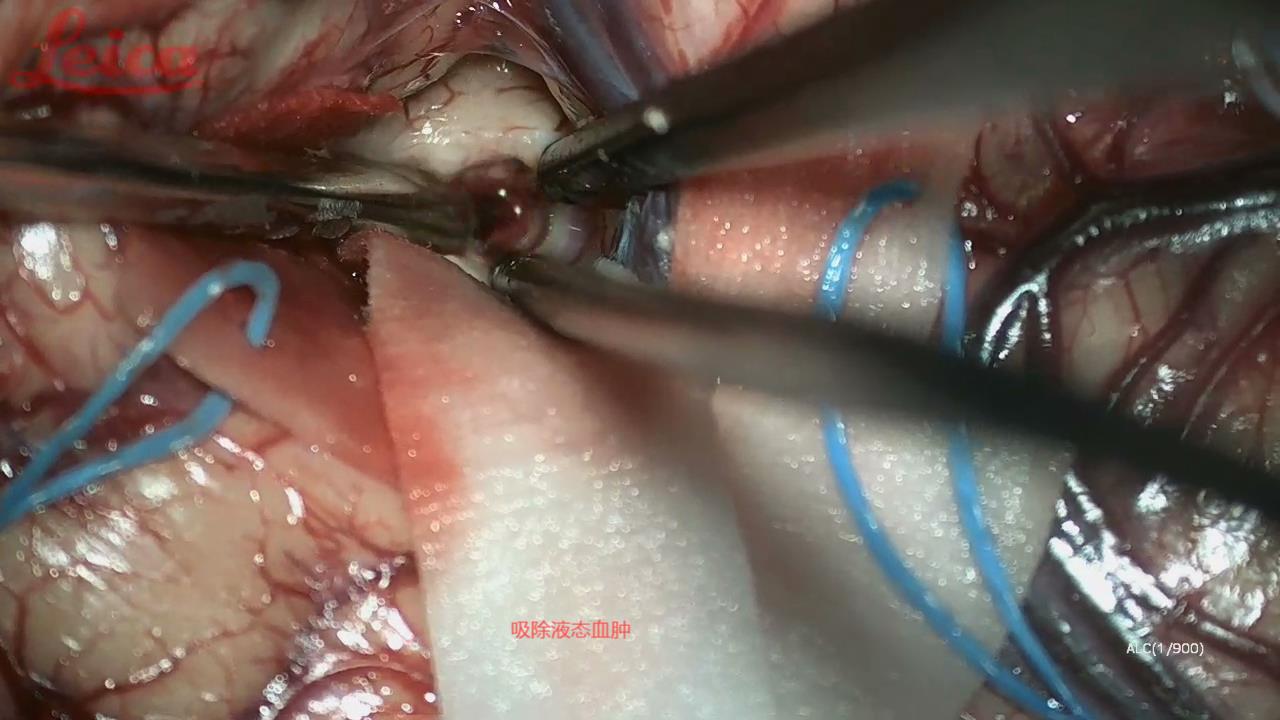

经外侧裂-岛叶造瘘清除血肿简要

经外侧裂-岛叶造瘘清除基底节出血